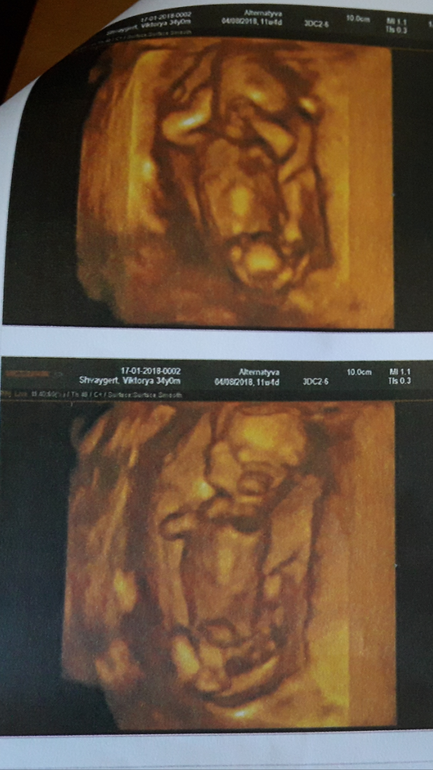

Мальчик или девочка ?

Статьи, видео о беременности, родах, информация о материнствеВот и весь вопрос). Кого вы видите? На узи 12 недель предположили девочку.

На девочку-лапулю похоже. Но рано еще судить))) Боже, какая милота растет внутри женщины. Берегите себя и лапулю!

Вот и мне похоже на девочку), личико девчачье). Знаю, бред несу). Спасибо за поддержку).